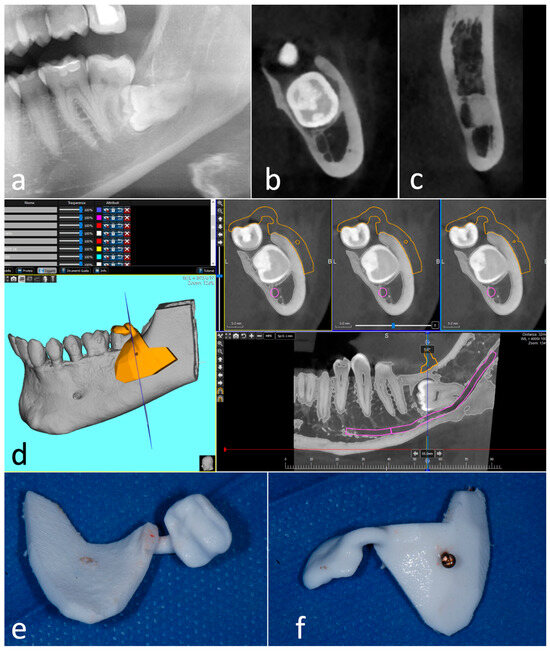

2. Description of the Cases